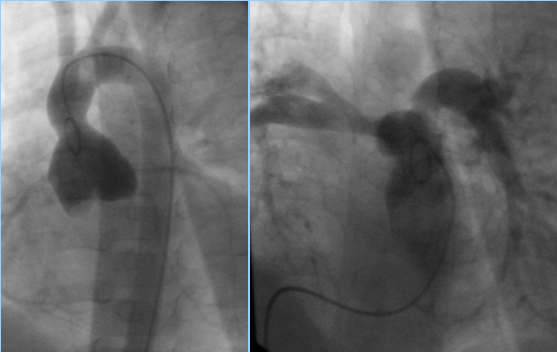

При ангиокардиографическом обследовании в 2007 году выявлена реканализация ДМЖП и стенозы устьев обеих легочных артерий.

Первым этапом выполнено эндоваскулярное закрытие ДМЖП устройством Amplatzer Membranous Septal Ventricular Occluder 6.0 мм

Операция: Закрытие реканализированного ДМЖП устройством Amplatzer Menbranous Septal Ventricular Occluder 6.0 мм